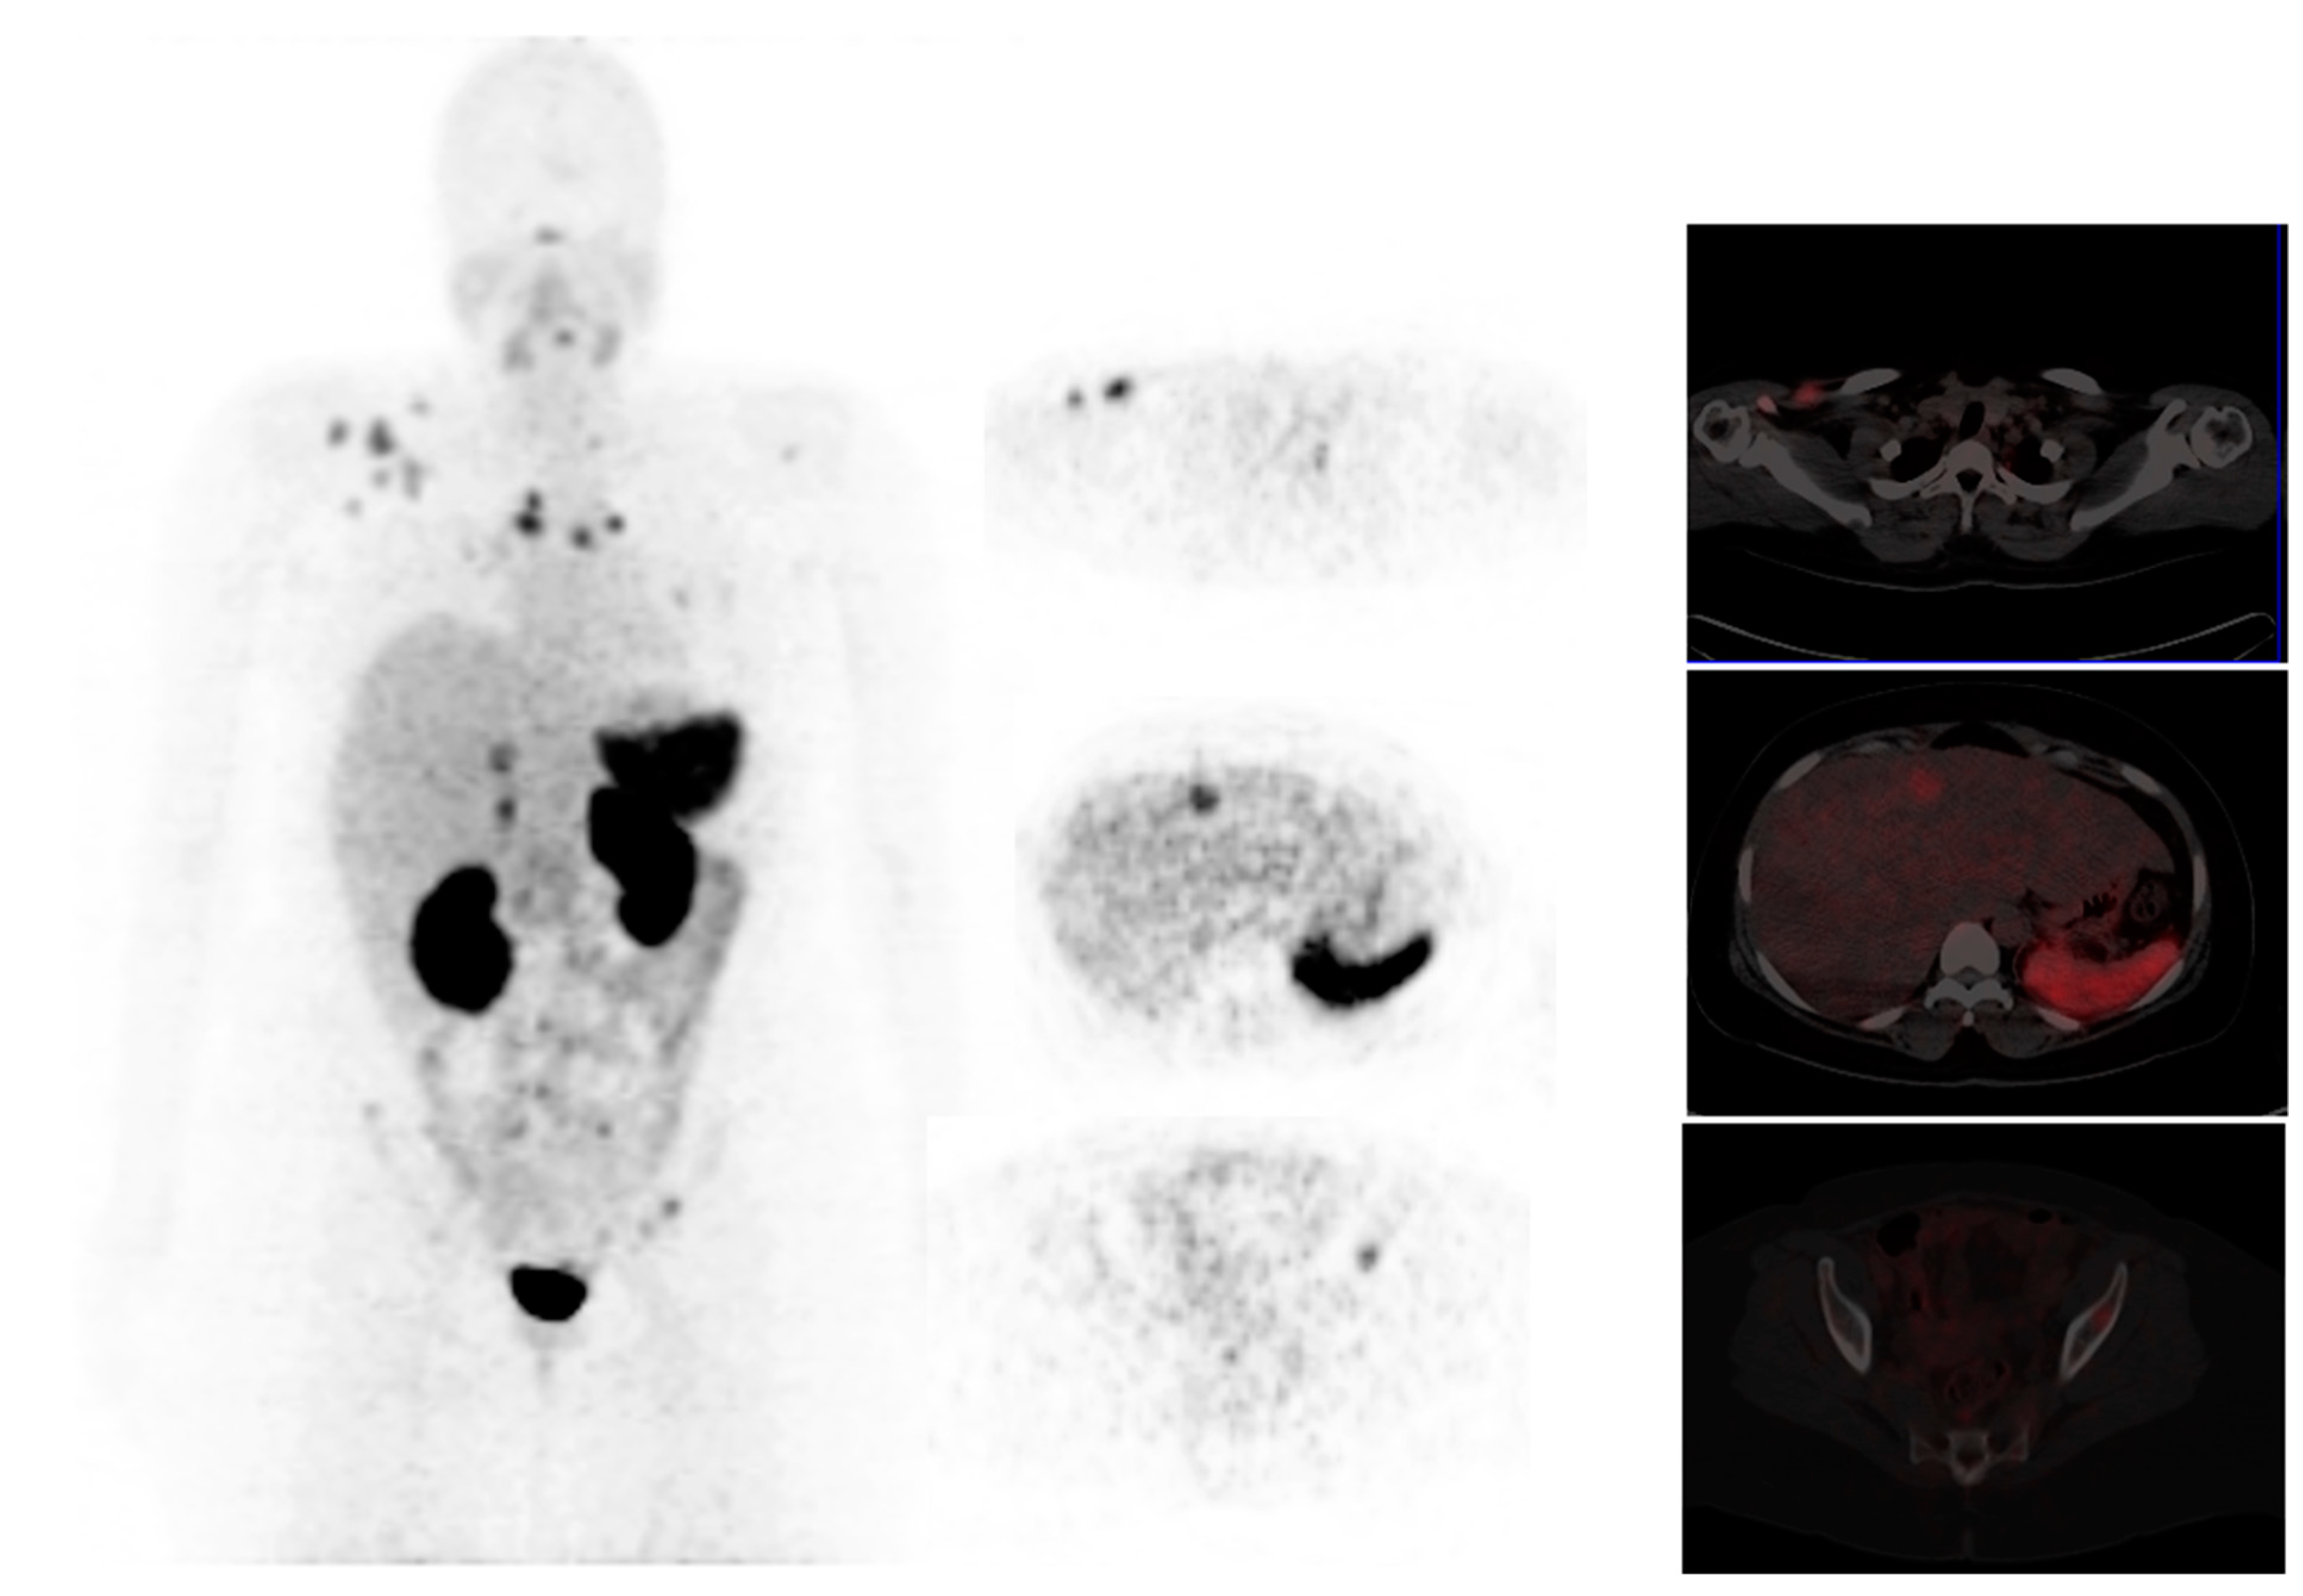

Somatostatin receptors (SSTR) are variably expressed in primary breast cancer tumors, and there is a positive correlation between several receptor subtypes (SSTR1, SSTR2, and SSTR4) and hormone receptor (HR) positive tumors [72]. Breast tumors expressing hormone receptors (ER, PR) have significantly lower FDG uptake than tumors that do not express HR. Breast cancers are known to demonstrate avidity on SSTR imaging, as shown in Figure 5. Nguyen et al. investigated 10 patients with ER+, PR+, and HER2- breast cancer patients with 68Ga-DOTATATE and 18F-FDG PET/CT and compared the findings with conventional imaging (bone scan and diagnostic CT) [73]. The total lesion detection rate of DOTATATE was comparable to FDG and conventional imaging for primary breast tumors and nodal and bone metastases; however, DOTATATE demonstrated a lower detection rate of visceral lesions compared with FDG. 68Ga-DOTATATE demonstrated higher uptake in 1 ER+ patient that underwent biopsy compared to FDG. Therefore STSR imaging may have a role in patients with poor FDG uptake and guide hormonal therapy. However, a study comparing 68Ga-DOTATATE with 18F-FES for this indication is warranted.

Figure 5.

A 39-year-old female with right breast invasive ductal carcinoma, PR negative and ER positive. She underwent a mastectomy, radiation therapy, chemotherapy, and hormonal therapy and was referred for a restaging PET/CT. 68Ga-DOTATATE imaging demonstrated metastatic involvement of the mediastinal- and axillary lymph nodes, lungs, liver- and skeletal system. Images provided by Dr. Janet Reed, Steve Biko Hospital, Pretoria.